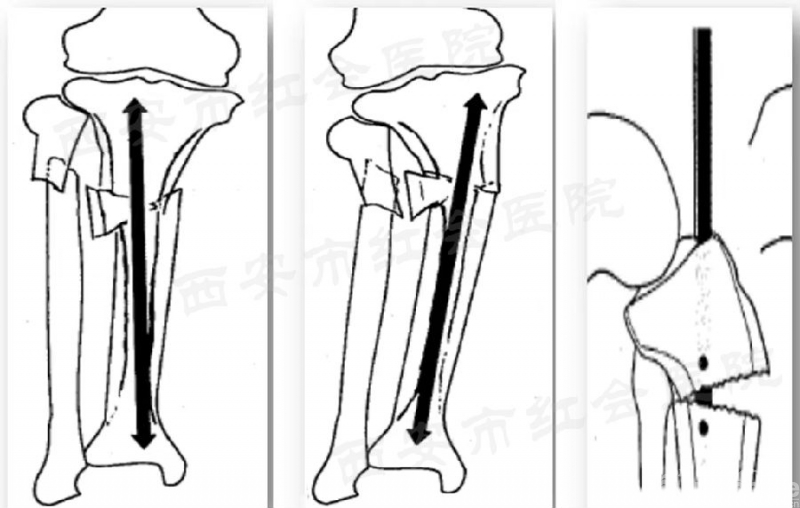

在冠状面上,进针点偏外会导致内翻畸形,而进针点偏内会外翻畸形;在矢状面上,进针点偏前会导致前凸畸形。

髓内钉有一个并发症,就是对半月板和关节软骨的损伤,而规避这一风险的最好方案就是进针点要精确。胫骨近端前缘的裸区(也叫安全区),长1-3cm的宽度,短边更小,切开可直接看到这个位置。